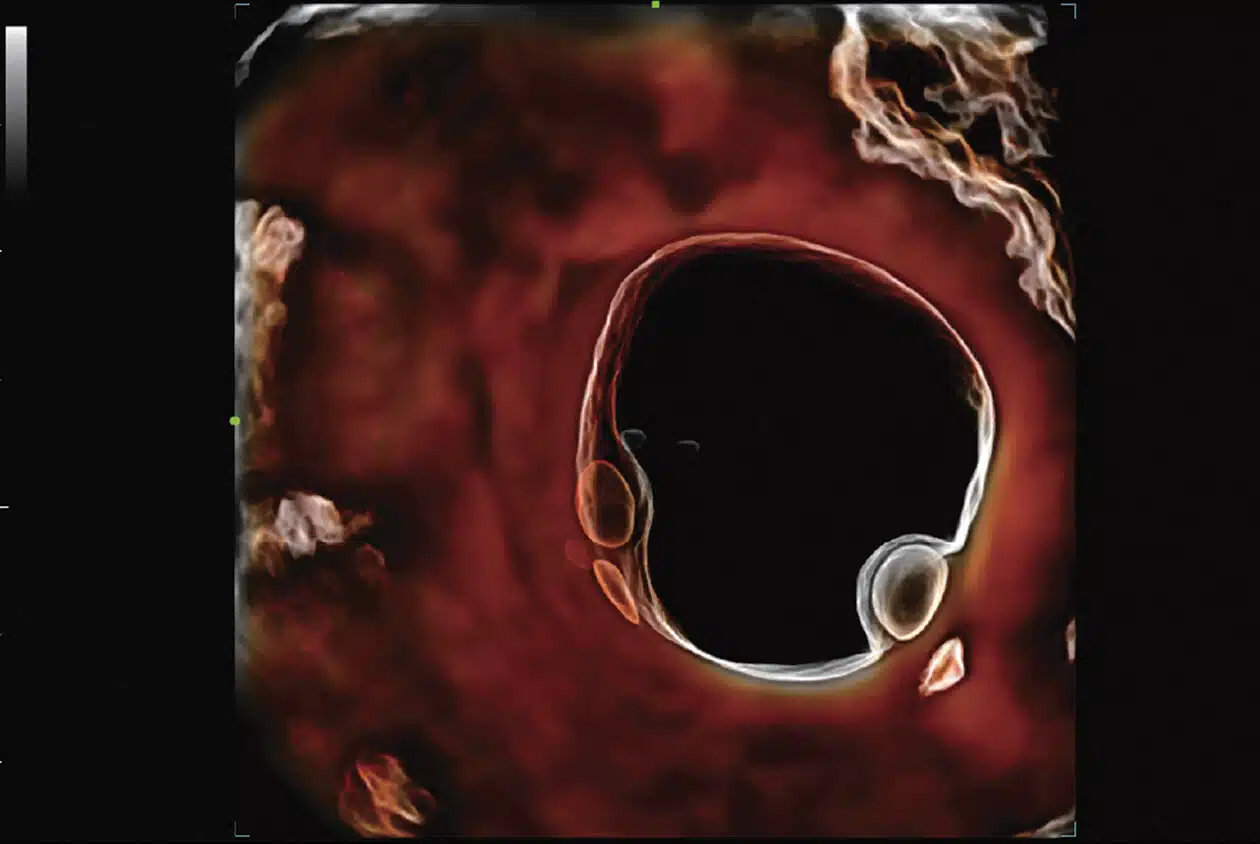

• Follicle-3D_Imagyn-I9.jpg

3D Follicle